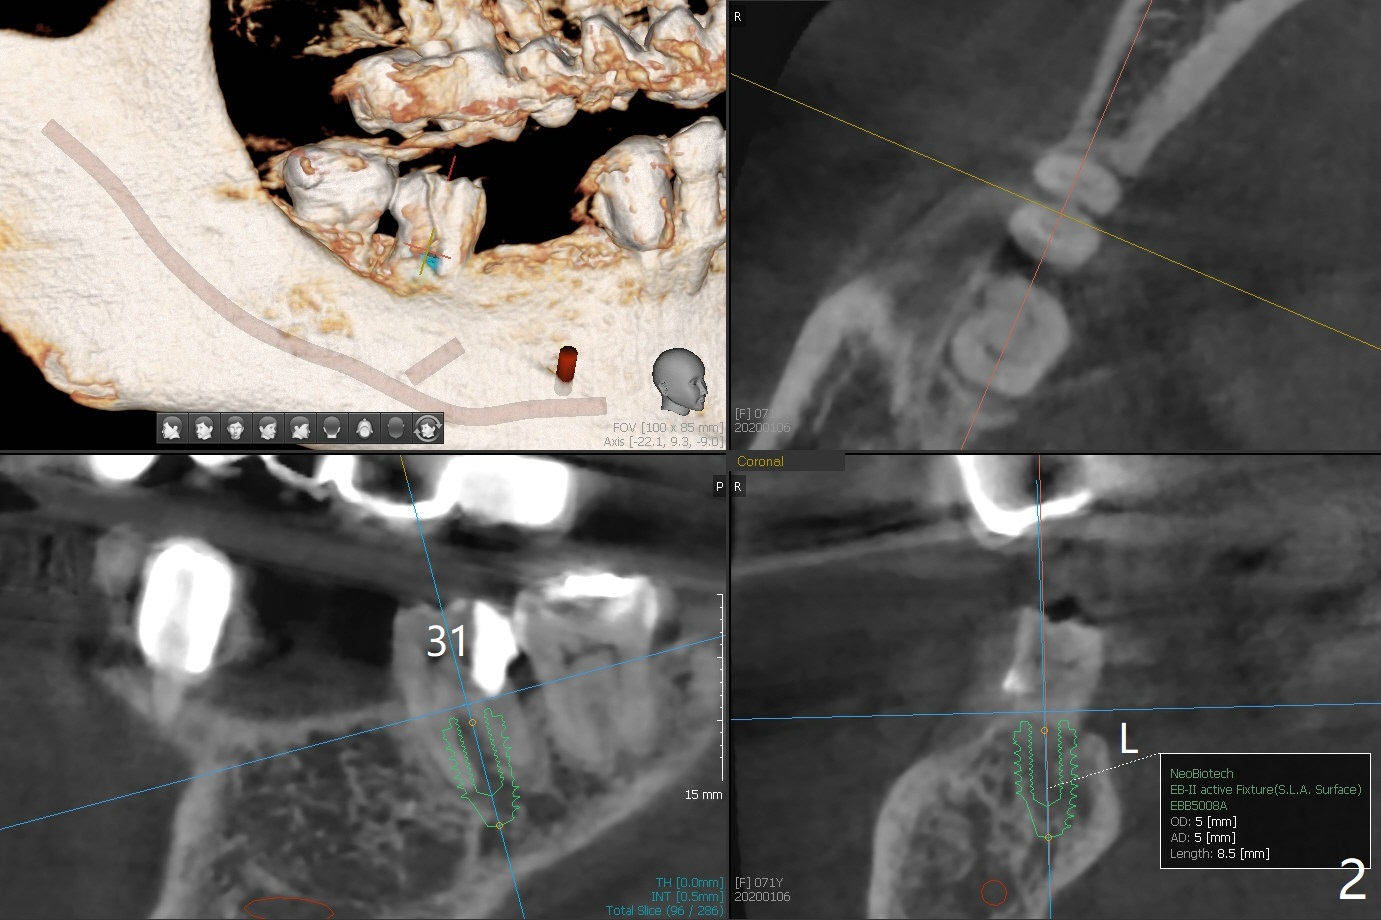

A 71-year-old woman has failed retainer at #31 (Fig.1). Implants will be placed at #31 and 29 for a FPD (Fig.2,3, as compared to Fig.4,5). The ridge at #29 is narrow with thick lingual plate. To avoid buccal deviation, coronal osteotomy overprep will be conducted.